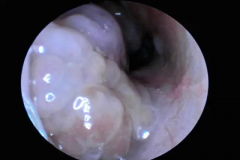

南京仁品耳鼻喉专科医院:鼻息肉(nasal polyps)是鼻腔及鼻窦黏膜在慢性炎症或变态反应等因素作用下,发生极度水肿肥厚并突入鼻腔形成的良性赘生物 ...[详情]